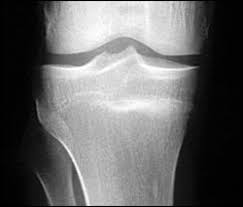

How are stress fractures diagnosed?